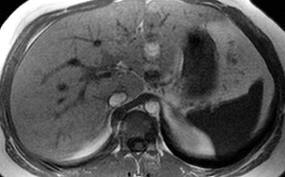

DDx for Non-enhancing Cystic Liver Lesions

Top Differential Diagnoses:

Biliary Hamartoma:

Fx:

NECT

CECT

MR Findings

Clinical Mx: